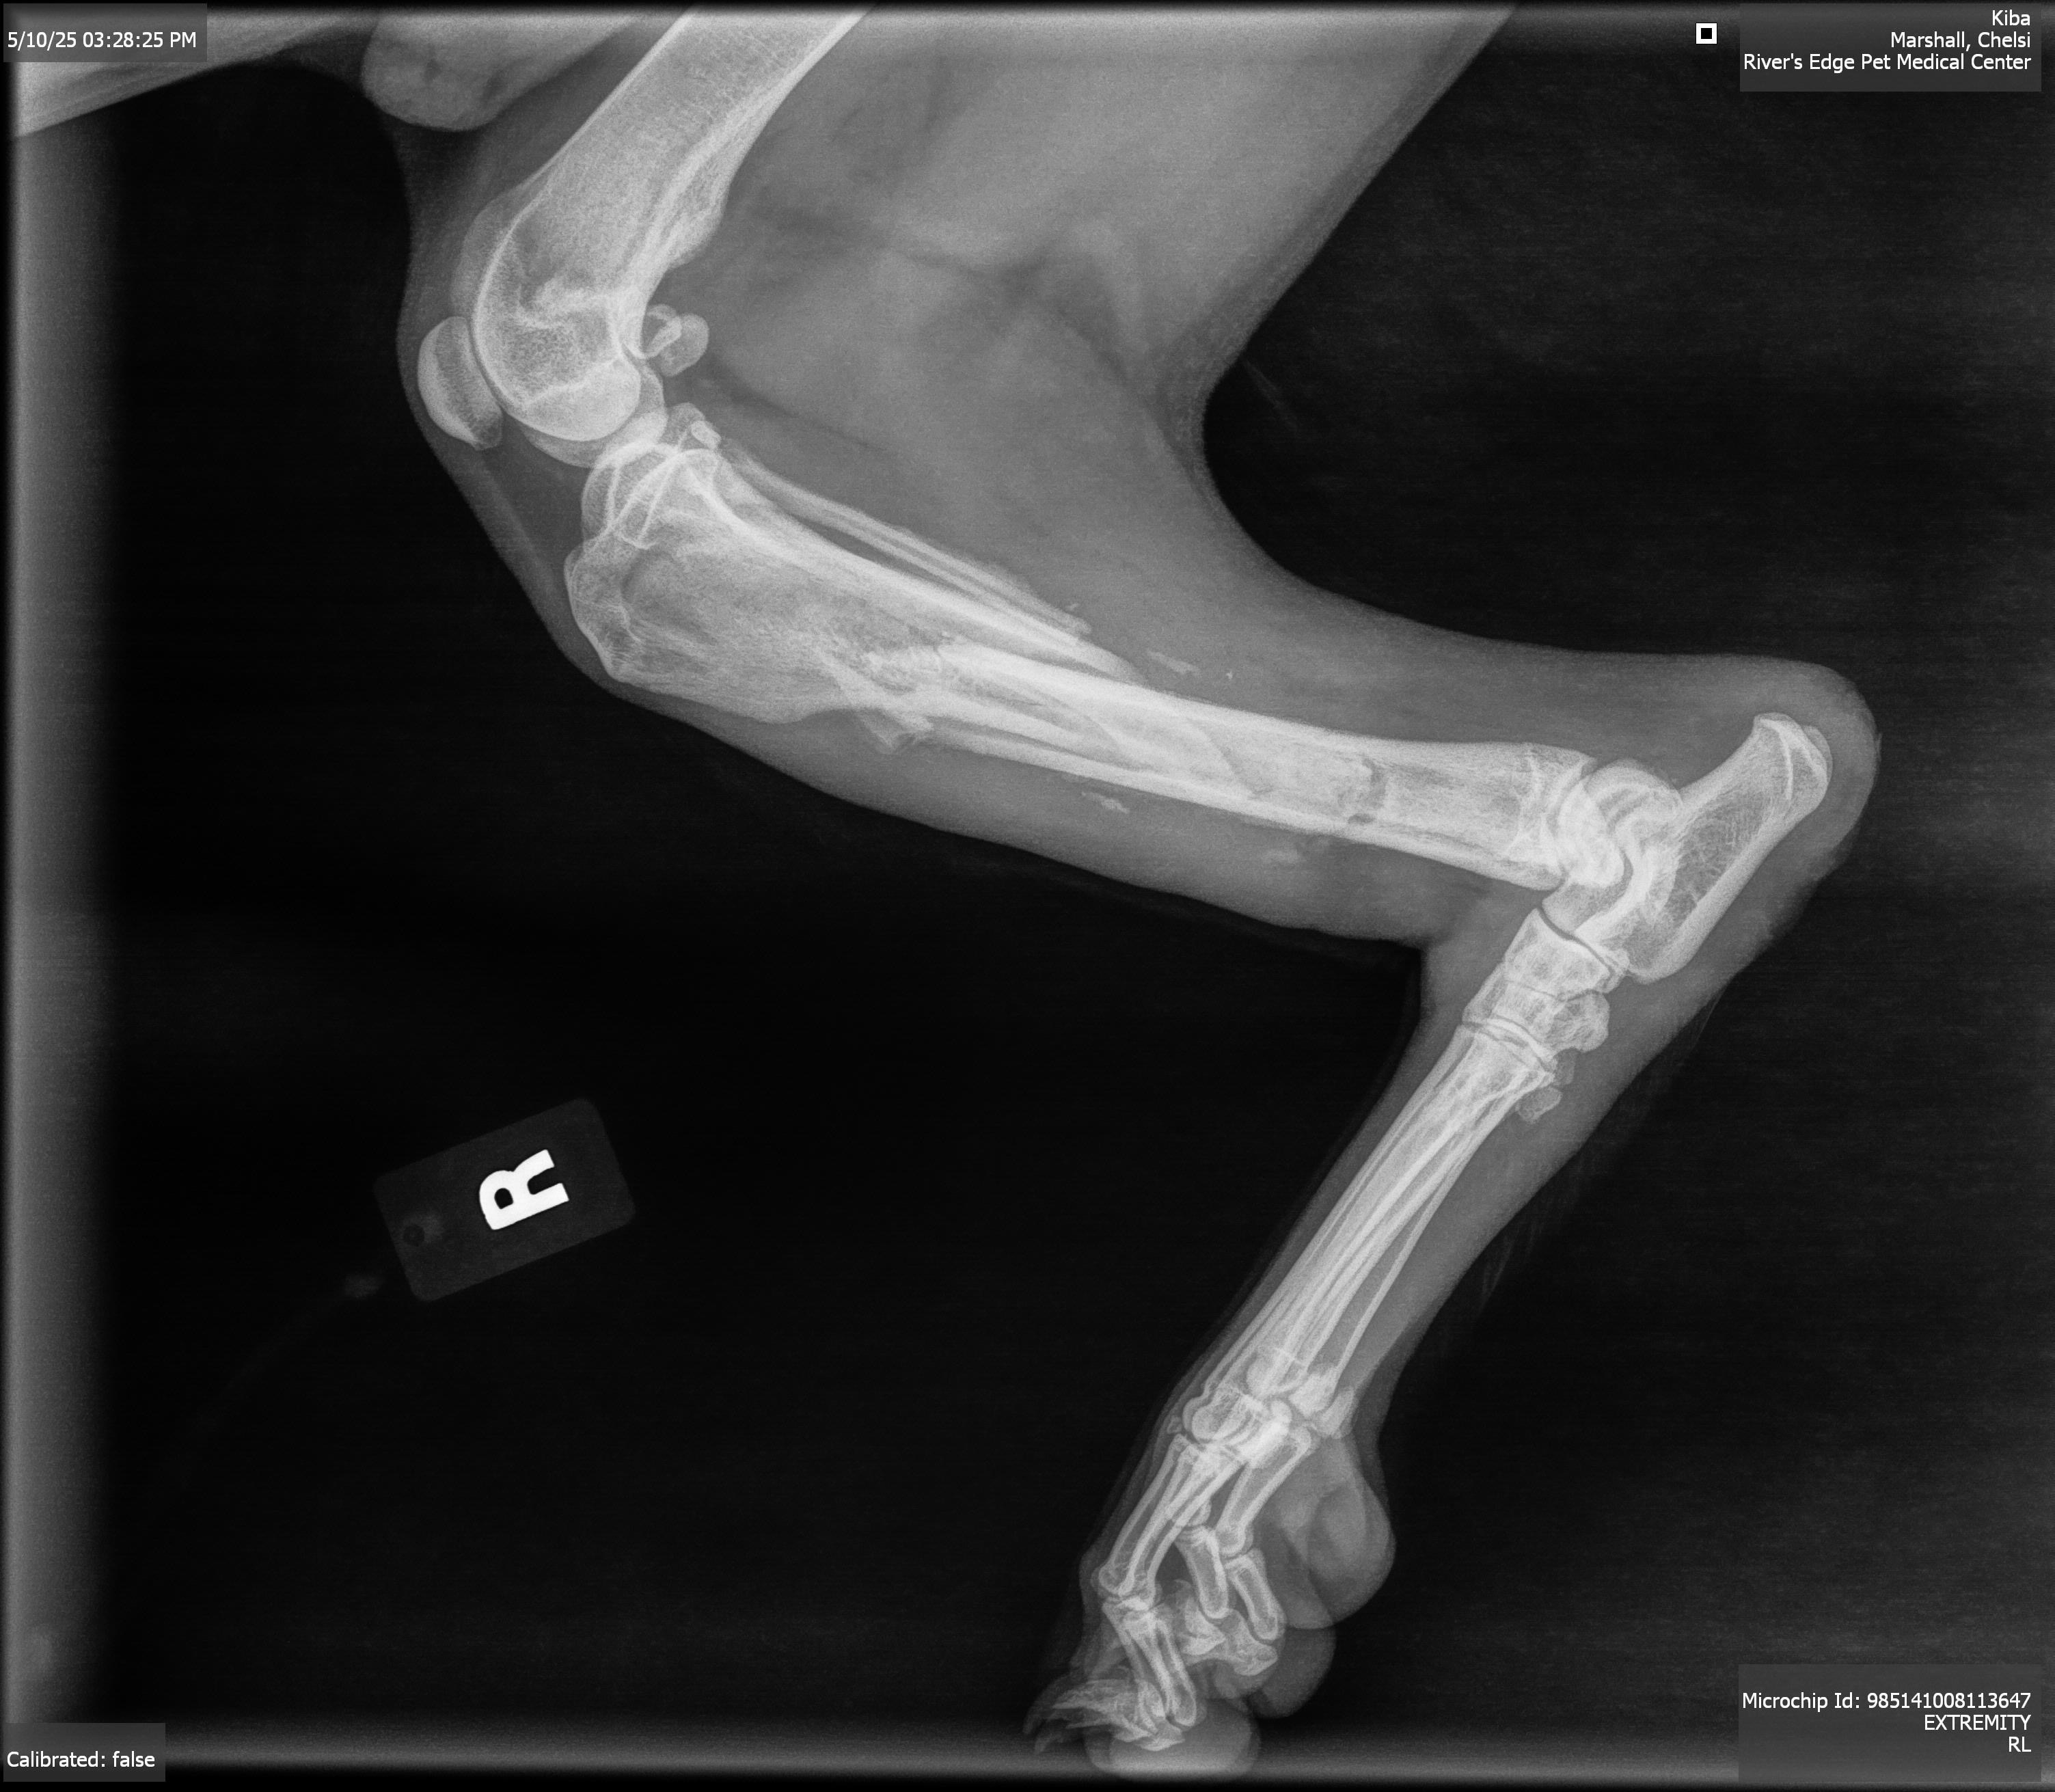

Update: Kiba had his appointment with the OSU veterinary hospital who will be doing the surgery and his leg is worse then we thought. His tibia is mangled and has calluses forming in the bone. The vet believes he was hit by a car the first day he went missing so there has been time for the bones to try and “heal”. So they are going to have to do a lot of work to try and fix his leg. I have added a photo of the itemized cost for the surgery. Please if anyone would like to help us get our boy back to health please donate. I appreciate every one of you more than words could ever express. If anyone would like to donate directly to OSU this is the number to call [phone redacted] and say it’s for Kiba and the owner is Chelsi Holmes.

Hi everyone, my name is Chelsi and a lot of you saw our story about our dog Kiba who was missing for almost 2 weeks. While our boy was gone, he got hurt and has multi bone spiral fracture to his tibia and fibula and is going to need surgery to fix his leg. This is going to be an expensive surgery and we could use any help that we can get to help Kiba get back to his happy, healthy self. I understand that these are trying times for everyone, but anything helps. His consultation for surgery is with OSU vet on Wednesday and I will post all of their findings and itemized list of what they are going to do for him and cost when I have it. I have added the pictures of his x rays that our vet took and pictures of his wounded leg before and after going into the vet.